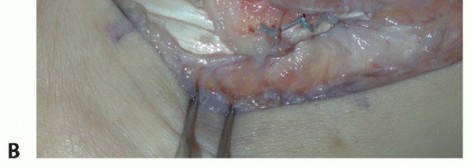

TECH FIG 1 • A. Intraoperative photograph of a left ankle (lateral approach) shows the peroneal tendons subluxing anteriorly (brevis is the gray arrowhead , longus is the white arrowhead , SPR is the black arrow). B. The peroneal tendons have been retracted anteriorly by the Penrose drain. Elevation of an anterior-based periosteal flap (outlined by dots) from the fibular groove has been completed. The black arrow shows the remnant of the SPR posteriorly. C. The tendons are relocated, after a groove-deepening procedure, into the recreated groove. The white dots outline the anteriorly based periosteal flap. It is then brought over to the posterior remnant of the SPR (black arrow). D. The flap is sutured to the remnant SPR with nonabsorbable sutures, completing the superior peroneal retinaculoplasty. |

| If a shallow or convex fibular groove is present, we typically perform a groove-deepening procedure. | |||

| Use a burr to deepen the groove 6 to 9 mm with all raw bony edges. The groove should extend from the fibular tip to 5 cm proximal. We use bone wax to smooth the groove. | |||

| Reduce the peroneal tendons and use the periosteal flap to contain the tendons, with the visceral side of the periosteum facing the tendons (TECH FIG 1C). | |||

| Suture the flap to the posterior remnant of the SPR with a series of 3-0 polybraided nonabsorbable sutures (TECH FIG 1D). | |||